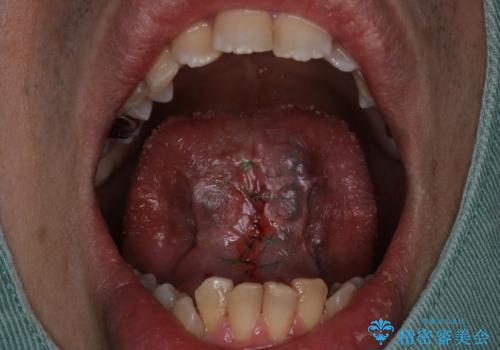

『即日手術』滑舌が悪いのを改善したい!

- 滑舌が気になるため舌小帯の切除を希望し来院されました。

ベロが動かせるようになってすごく喜ばれておりました。